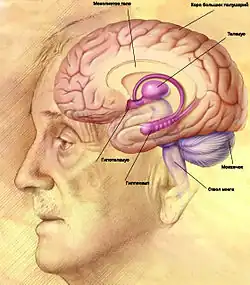

Строение головного мозга

Объём мозга большинства людей находится в пределах 1250—1600 кубических сантиметров и составляет 91—95 % ёмкости черепа. В головном мозге различают пять отделов: продолговатый мозг; задний, включающий в себя мост, мозжечок и эпифиз; средний; промежуточный; и передний мозг, представленный большими полушариями. Наряду с приведённым выше делением на отделы, весь мозг разделяют на три большие части:

- полушария большого мозга;

- мозжечок;

- ствол мозга.

Продолговатый мозг

Продолговатый мозг (лат. medulla oblongata) развивается из пятого мозгового пузырька (дополнительного). Продолговатый мозг является продолжением спинного мозга с нарушенной сегментарностью. Серое вещество продолговатого мозга состоит из отдельных ядер черепных нервов. Белое вещество — это проводящие пути спинного и головного мозга, которые тянутся вверх в мозговой ствол, а оттуда в спинной мозг.

Мост

Мост (лат. pons) лежит выше продолговатого мозга. Это утолщённый валик с поперечно расположенными волокнами. По центру его проходит основная борозда, в которой лежит основная артерия головного мозга. По обе стороны борозды имеются заметные возвышения, образованные пирамидными путями. Мост состоит из большого количества поперечных волокон, которые образуют его белое вещество — нервные волокна. Между волокнами немало скоплений серого вещества, которое образует ядра моста. Продолжаясь до мозжечка, нервные волокна образуют его средние ножки.

Мозжечок

Мозжечок (лат. cerebellum) лежит на задней поверхности моста и продолговатого мозга в задней черепной ямке. Состоит из двух полушарий и червя, который соединяет полушария между собой. Масса мозжечка 120—150 г.

Средний мозг

Покров среднего мозга (лат. mesencephalon) лежит над его крышкой и прикрывает сверху водопровод среднего мозга. На крышке содержится пластинка покрышки (четверохолмие). Два верхних холмика связаны с функцией зрительного анализатора, выступают центрами ориентировочных рефлексов на зрительные раздражители, а потому называются зрительными. Два нижних бугорка — слуховые, связанные с ориентировочными рефлексами на звуковые раздражители. Верхние холмики связаны с латеральными коленчатыми телами промежуточного мозга с помощью верхних ручек, нижние холмики — нижними ручками с медиальными коленчатыми телами.

Большие полушария

Головной мозг разделён бороздой на два больших полушария (Hemisphaerium cerebri): левое и правое. В большие полушария входят: кора большого мозга (плащ), базальные ганглии, обонятельный мозг и боковые желудочки. Полушария мозга разделены продольной щелью, в углублении которой содержится мозолистое тело, которое их соединяет. На каждом полушарии различают следующие поверхности:

В каждом полушарии есть части, которые наиболее выступают: впереди, — лобный полюс, сзади — затылочный полюс, сбоку — височный полюс. Кроме того, каждое полушарие большого мозга разделяется на четыре большие доли: лобную, теменную, затылочную и височные. В углублении боковой ямки мозга лежит небольшая доля — островок. Полушарие поделено на доли бороздами. Самая глубокая из них — боковая, или латеральная, ещё она называется сильвиевой бороздой. Боковая борозда отделяет височную долю от лобной и теменной. От верхнего края полушарий опускается вниз центральная борозда, или борозда Роланда. Она отделяет лобную долю мозга от теменной. Затылочная доля отделяется от теменной только со стороны медиальной поверхности полушарий — теменно-затылочной бороздой.